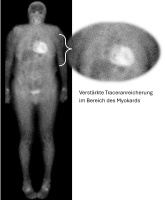

Szintigraphie

Abbildung 2: DPD-Scan, Perugini-Grad-3